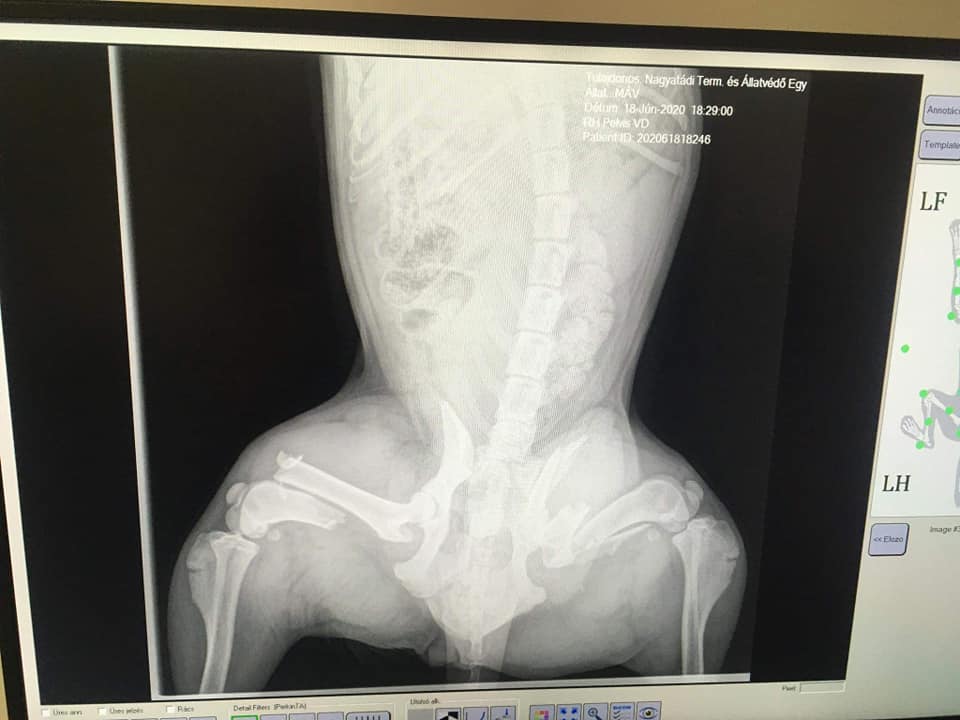

Eine weitere sehr traurige Nachricht erreichte uns aus Ungarn. (Nagyatád) Vor 2 Tagen wurde die kleine Máv von einem Zug erfasst. Ihr wurden dadurch beide Beine gebrochen. Die junge Hündin lag 2 Tage zwischen den Gleisen, man dachte, sie sei tod.

Doch Máv lebte, schwer verletzt und mit grossen Schmerzen. Sie musste so schlimme Ängste aushalten! Täglich rauschten mehrere Züge an ihr vorbei und sie konnte sich selber nicht davon bewegen. Sie ist nun in unserer Obhut und einige Operationen werden nötig sein, um die kleine Seele zu retten.